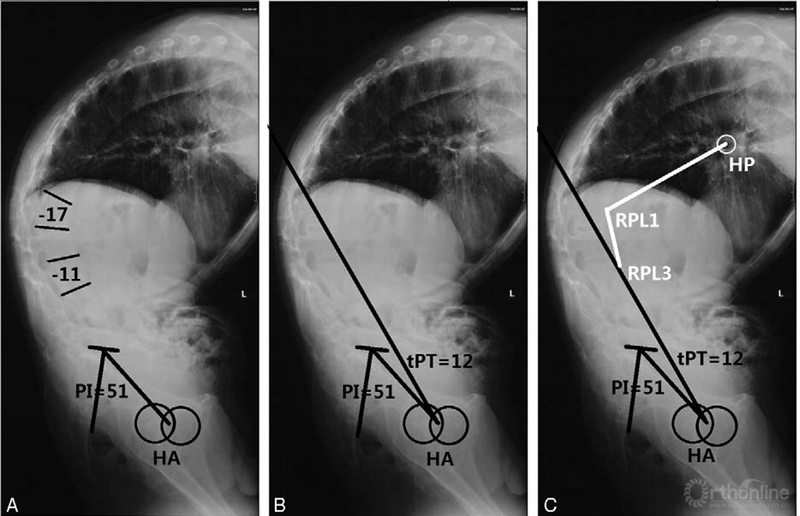

骨盆映射角(pelvic incidence,PI)正常在成年后恒定不变,文献报道PI值与AS单节段腰椎截骨矫形术后矢状位失衡有较大的相关性,高PI值对AS患者畸形的影响如下示意图所示。

图9 上 高PI值患者矢状位失衡更加明显; 下 高PI值患者实现矢状位平衡需要的截骨角度也较大

(图片资料摘自Debarge等Radiological analysis of ankylosing spondylitis patients with severe kyphosis before and after pedicle subtraction osteotomy, Eur Spine J, 2010, 19(1):65-70.)